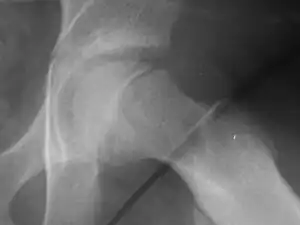

| X-ray showing a slipped capital femoral epiphysis, before and after surgical fixation. | |